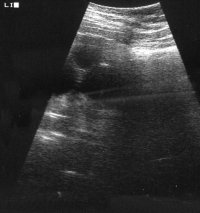

Bei einer 16-jährigen Jugendlichen wurde wegen Flankenschmerzen und sonographischem Verdacht auf einen linksseitigen zystischen Nierentumor die Freilegung durchgeführt (Abbildung 3). Dabei fand sich ein zystischer Tumor (Abbildung 4). Die histologische Untersuchung ergab eine multizystische, dysplastische Nierendegeneration.

Da die unilaterale multizystische Nierendysplasie nicht immer vergrößert ist, fallen derartige Tumoren unter Umständen erst im Erwachsenenalter anlässlich Untersuchungen aufgrund anderer Erkrankungen auf. Die Organe werden zumeist wegen der Differentialdiagnose zum zystischen Nierenzellkarzinom entfernt.